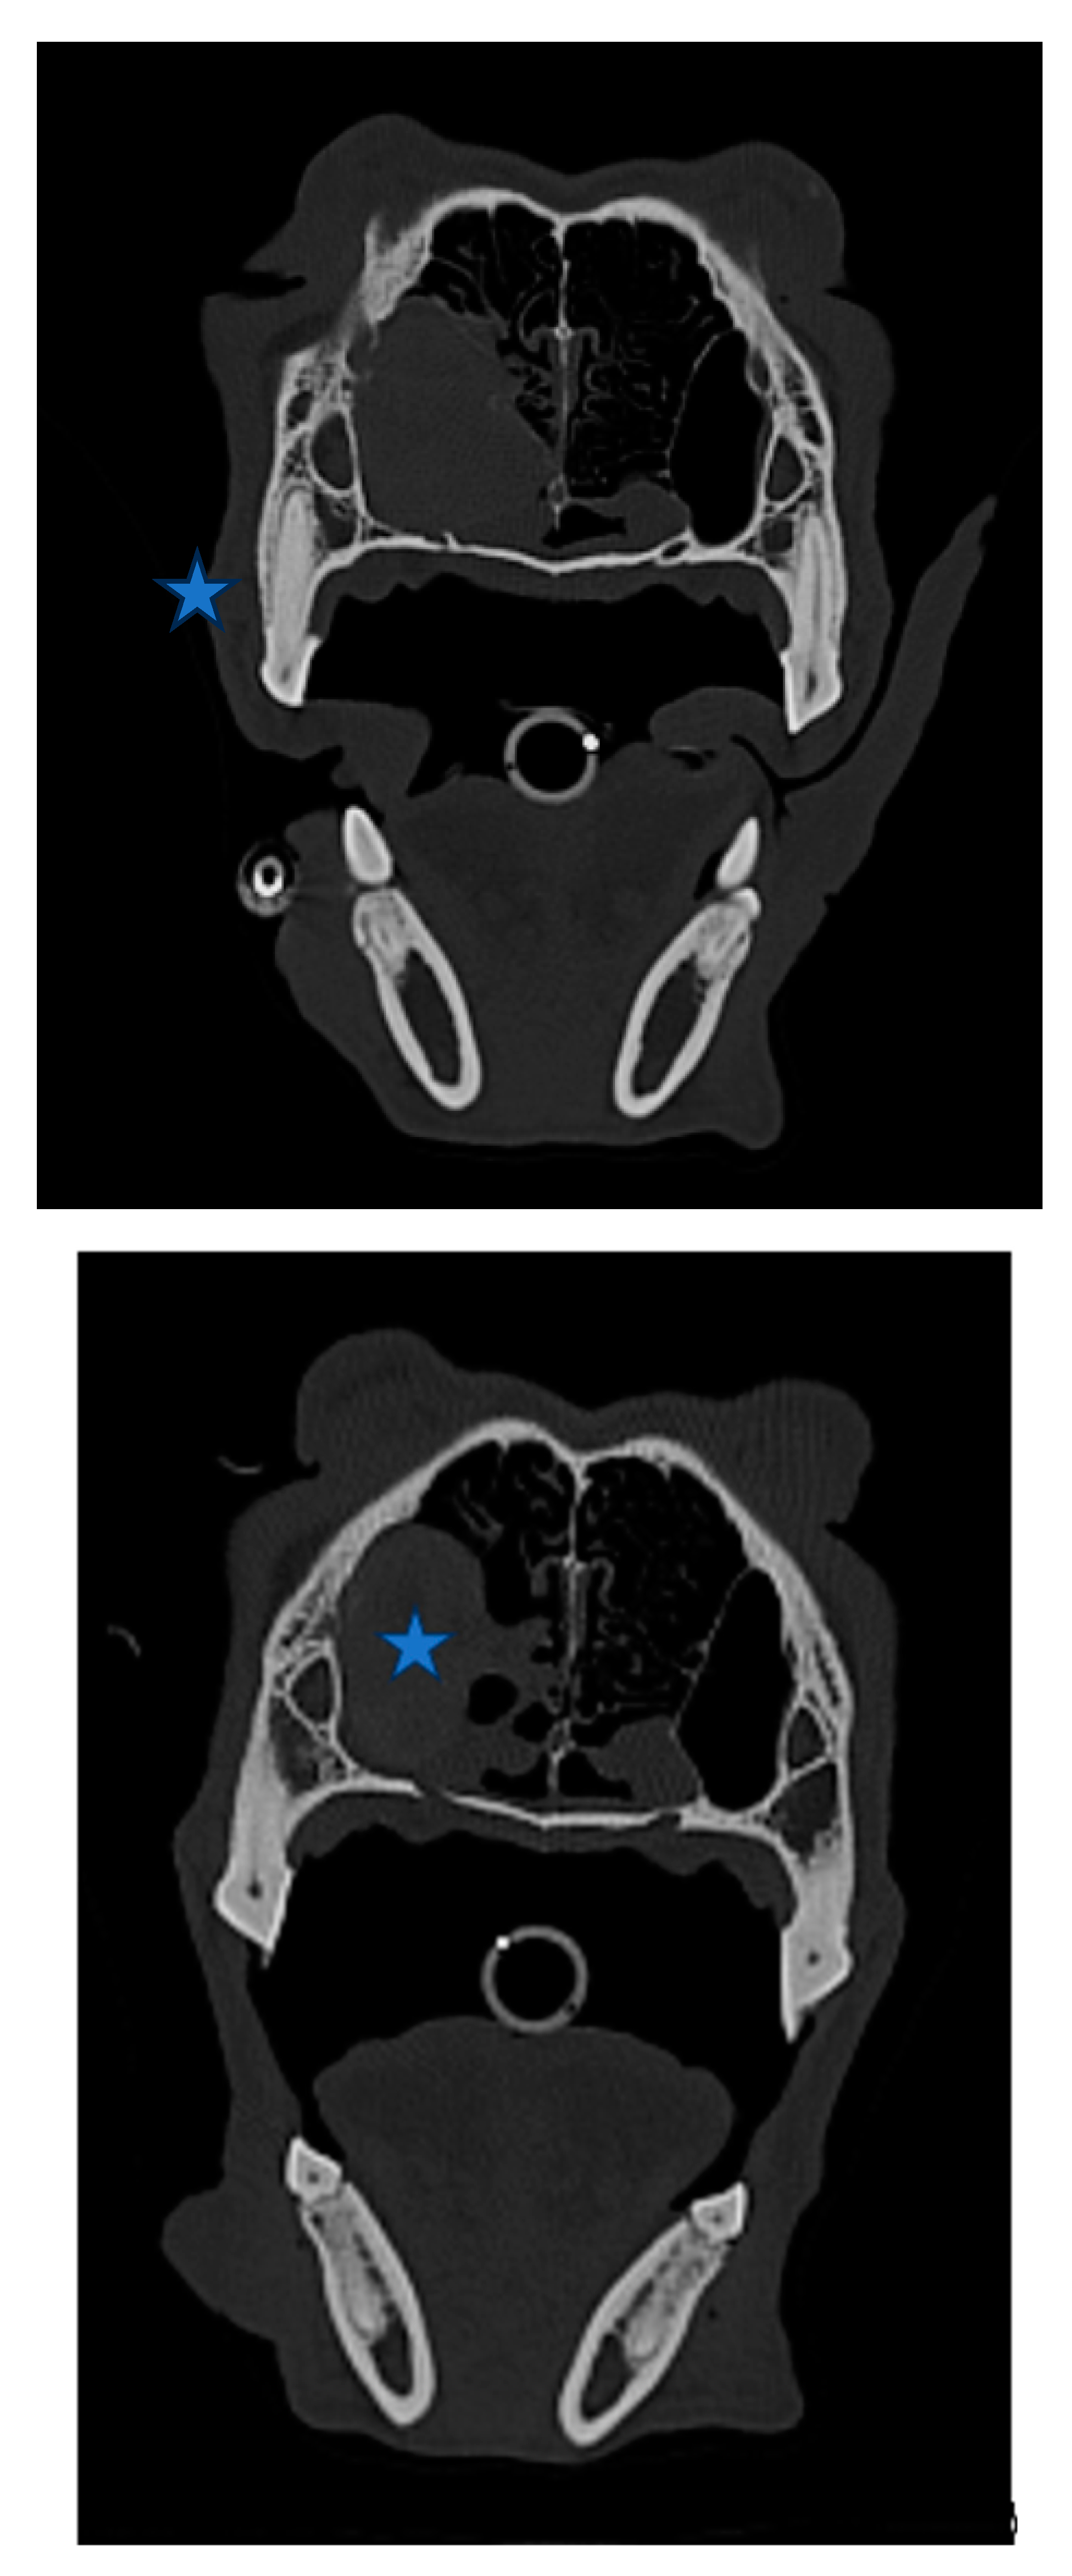

Figure 1. (A,B,C,D). Cellularity was high and cell shedding was very severe, although cells with a very high degree of malignancy were not observed. The cell integrity of the aspirate was very high, and the blood was severely infiltrated. Various types of nasal epithelial cells, such as columnar ciliated epithelium, columnar epithelium, and goblet cells, were observed in large and small groups. Neutrophils were observed in small numbers. Moderate nuclear anisotropy was observed, and three small nucleoli were clearly observed in a thick chromatin pattern. A basophilic amorphous substance thought to be nasal exudate was observed, and many melanin granules and eosinophilic granules were observed in the background. Perinuclear vacuoles, which are mainly observed in squamous cell carcinoma cells, were observed. Considering this comprehensively, the possibility of nasal carcinoma was considered, and histopathological examination was required for confirmation. Specimen: nasal cavity; single; size 5*2*3cm; incisional.